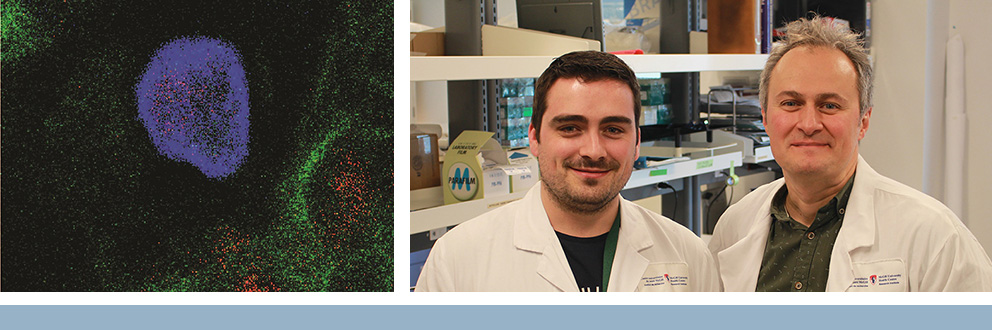

Régénérer les poumons endommagés : travaux de recherche importants visant à trouver un traitement curatif pour la MPOC

Les Drs Ben Smith et Larry Lands ainsi que Jun Ding, Ph. D., tous trois chercheurs au sein du Programme de recherche translationnelle sur les maladies respiratoires (programme RESP) à l’Institut de recherche du Centre universitaire de santé McGill (IR-CUSM), ont reçu le prestigieux prix du Concours Trottier-Webster d’innovation en recherche de l’IR-CUSM 2023. Les membres de cette équipe vont mettre en commun les connaissances et l’expérience acquises dans leur domaine respectif, soit les maladies respiratoires, les nanoparticules et l’apprentissage automatique pour mener une étude d’avant-garde. Leur projet a recours aux thérapies à base d’ARN, combinées avec les nanoparticules lipidiques. Leurs travaux auront pour objectif de déterminer si, dans le cas d’une personne atteinte de la maladie pulmonaire obstructive chronique (MPOC) présentant des signes d’« épuisement », les cellules souches des voies respiratoires peuvent être reprogrammées et redevenir plus fonctionnelles.